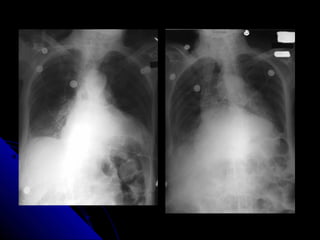

CCHHFF

CCaarrddiioommeeggaallllyy..

UUppppeerr lloobbee ddiivveerrssiioonn..

KKeerrlleeyy--BBlliinneess..

PPlleeuurraall eeffffuussiioonn..

BBaattwwiinngg eeddeemmaa..

37 CCHHFF CCaarrddiioommeeggaallllyy.. UUppppeerr lloobbee ddiivveerrssiioonn.. KKeerrlleeyy--BBlliinneess.. PPlleeuurraall eeffffuussiioonn.. BBaattwwiinngg eeddeemmaa..